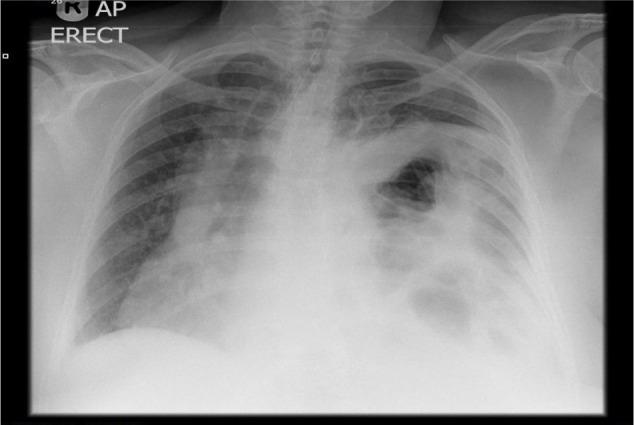

This is a rare case report of acute pancreatitis secondary to a massive incarcerated paraoesophageal hernia. The pathogenesis resulted from obstruction of the distal pancreatic duct after displacement of the pancreatic head and body into the thorax as part of a Type IV paraoesophageal hernia. Although this condition is rare, the patient made steady progress following laparotomy and open repair of hernia. She made a good recovery after prompt therapy, therefore, this report can be a guide to the diagnosis and treatment of similar conditions.

这是一例罕见的因巨大嵌顿性食管旁疝继发急性胰腺炎的病例报告。发病机制是作为IV型食管旁疝的一部分,胰头和胰体移位至胸腔后导致远端胰管梗阻。尽管这种情况罕见,但患者在剖腹手术和疝修补术后病情稳步好转。经过及时治疗,她恢复良好,因此,本报告可为类似病症的诊断和治疗提供指导。